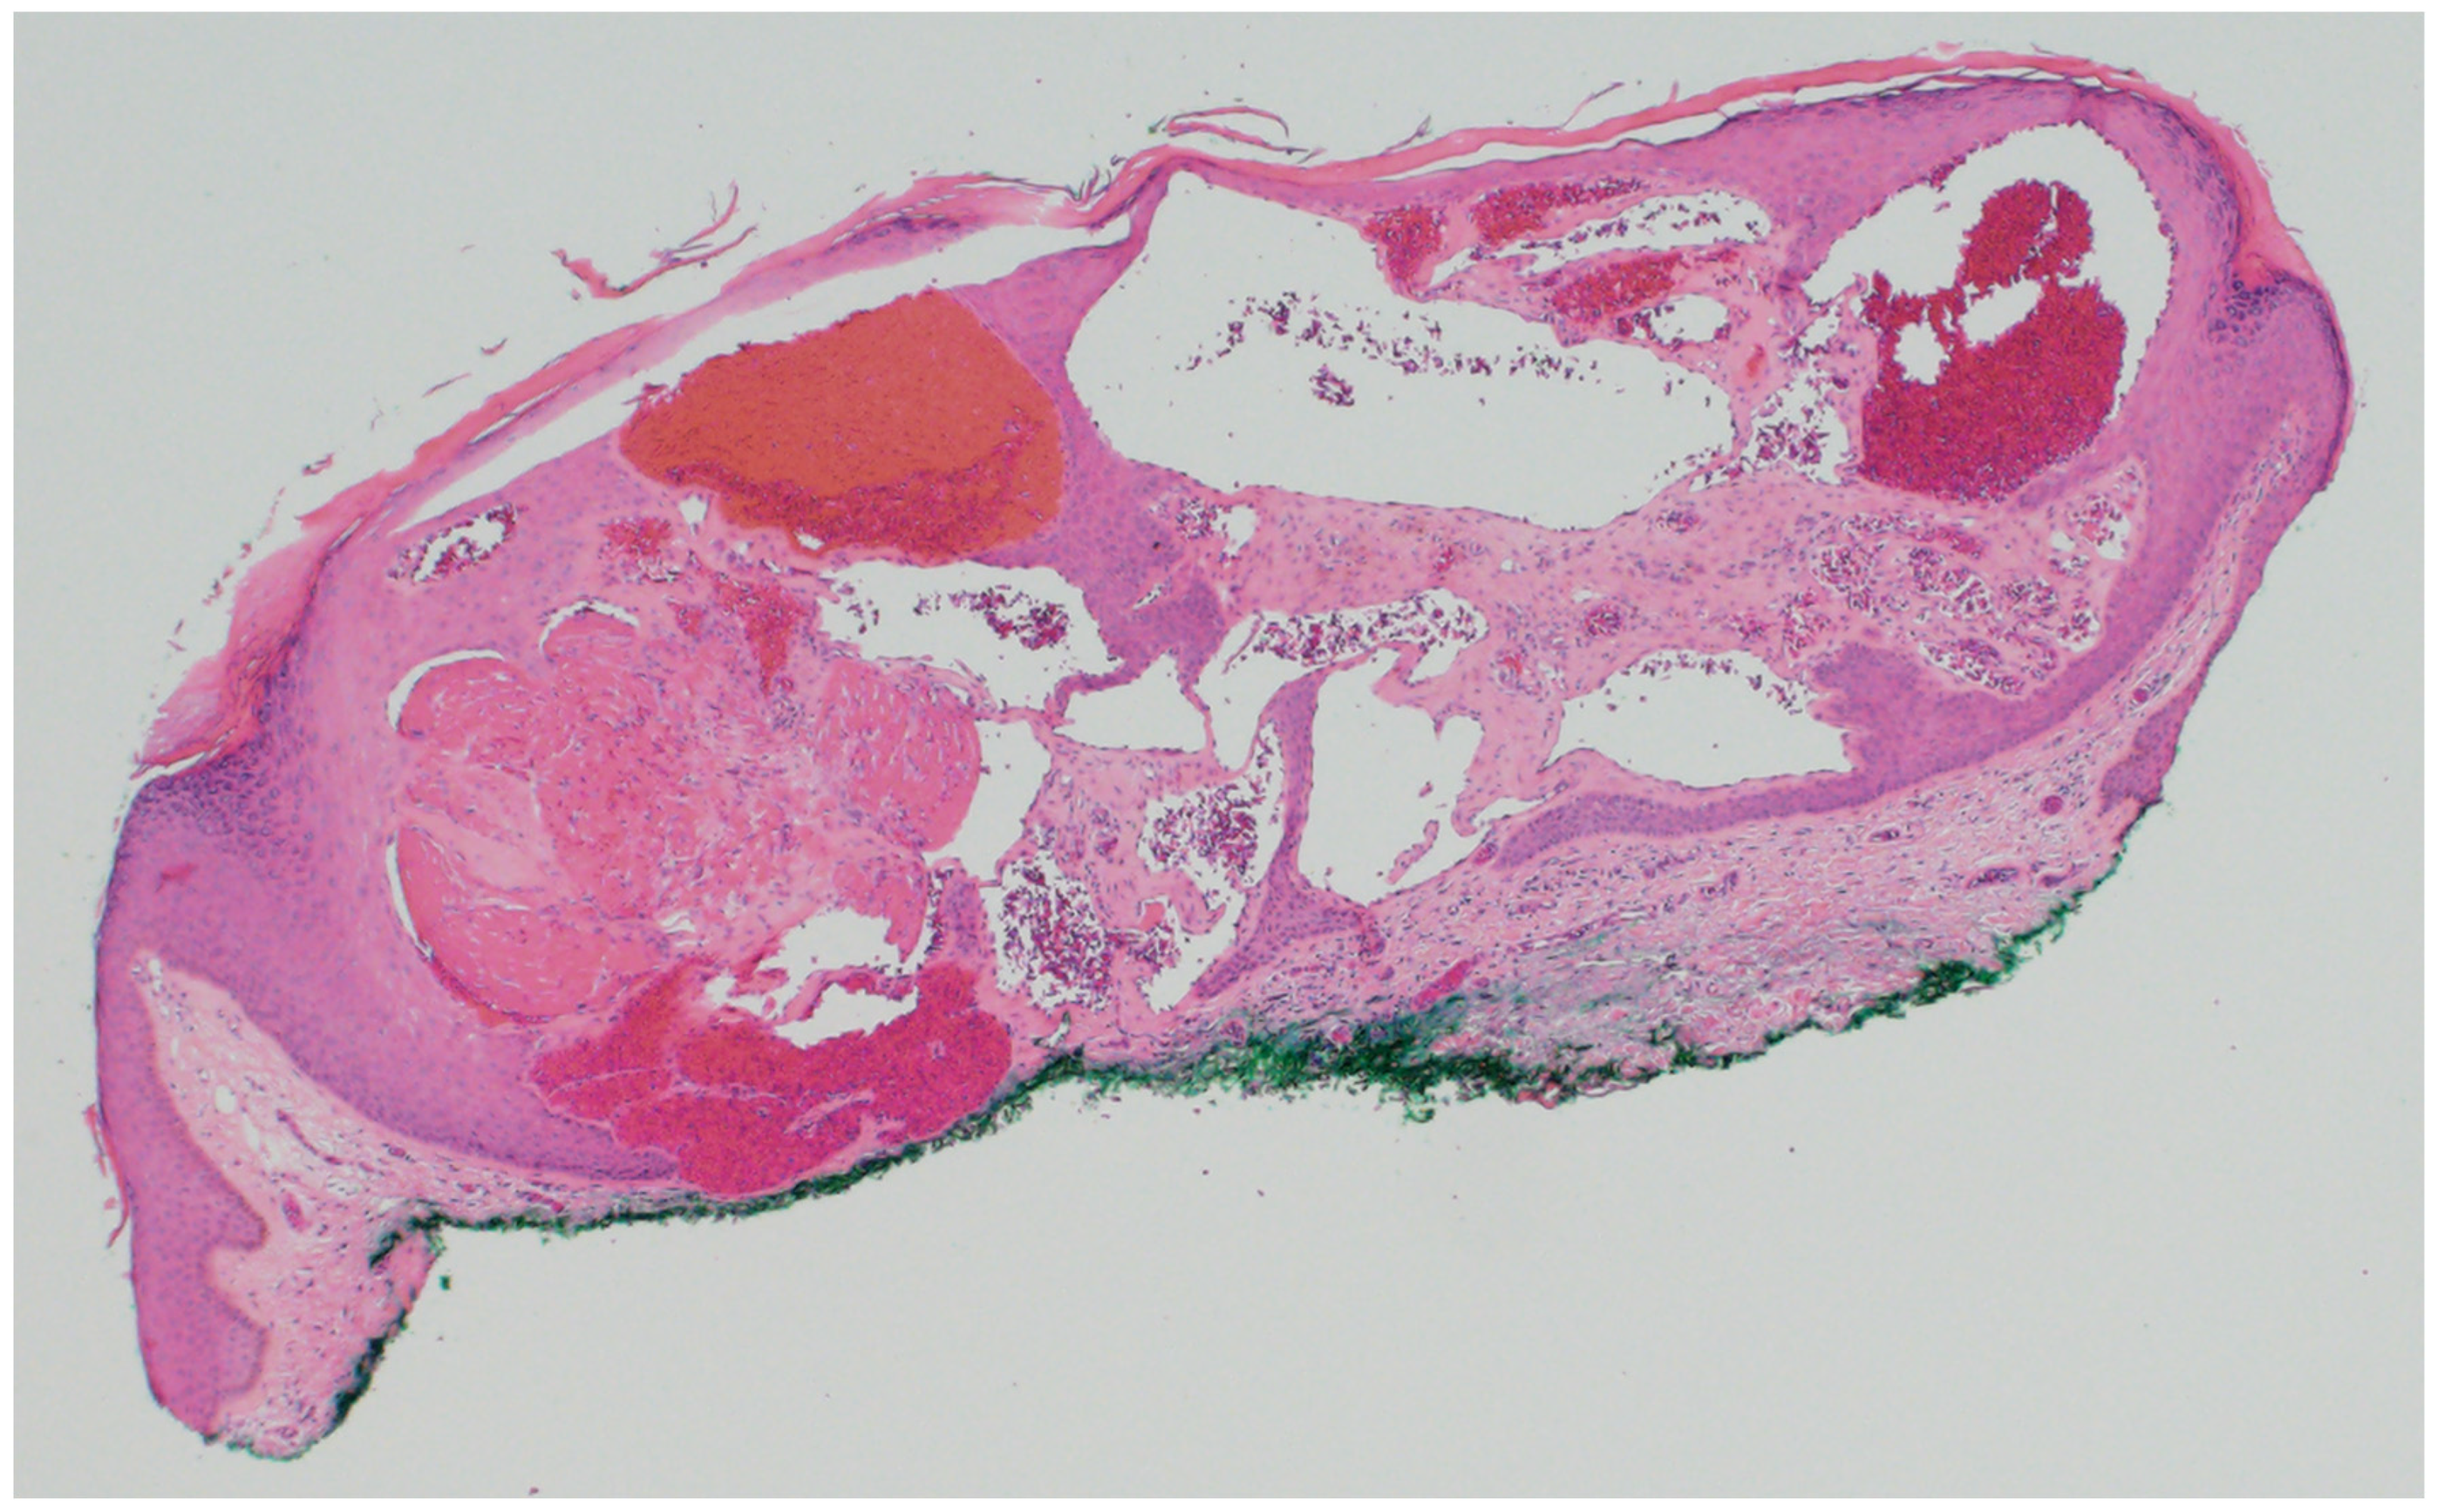

4.1. Cylindroma/Spiradenoma